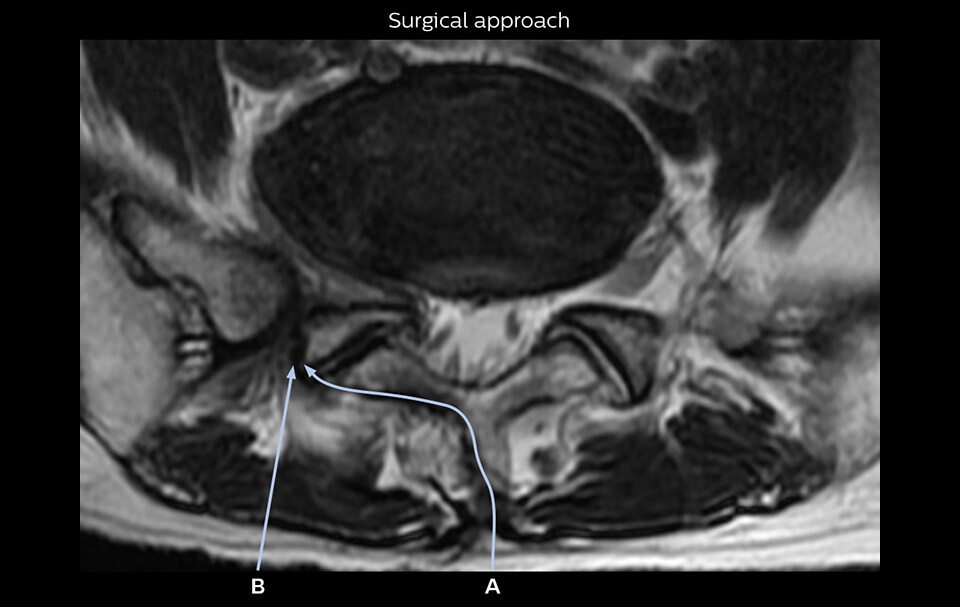

“Recently, the two surgical methods extreme and oblique lateral interbody fusion (XLIF and OLIF) have become mainstream for minimally invasive treatment of lumbar spinal canal stenosis and intervertebral foramen stenosis. With these surgical techniques, the spine is approached from the flank, and prior knowledge of the exact anatomy of the lumbosacral plexus would be extremely helpful. To that end, high slice resolution (less than 1 mm acquisition) that enables sharper sagittal MPR images will be needed.”

“Although symptoms of typical disc herniation and atypical hernia are very similar, the actual site of herniation is different. It is therefore important to characterize the nerve’s condition both inside and outside of the intervertebral foramina. “Conversely, if we see no abnormality in NerveVIEW, we can assume at least that there is no severe condition that requires surgery. Like this, it can help us avoid unnecessary surgery. NerveVIEW can have a tremendous impact in this way.”

“NerveVIEW is really useful for those cases where a nerve disorder is strongly suspected based on the clinical examination but our regular MRI images do not show any findings. These atypical herniations and spinal canal stenosis, occurring in 5% to 15% of the total lumbar herniation/stenosis cases are our main target when using NerveVIEW,” says Dr. Yabuki.